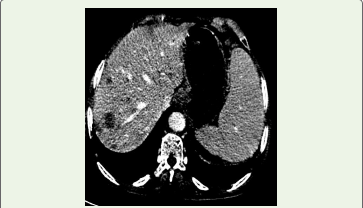

The mass showed extension into the proximal and mid left ureter with resultant dilatation, while the distal ureter appeared normal. An additional lesion was noted at the left vesicoureteric junction, producing a filling defect within the urinary bladder [Figure 2]. Enlarged left renal hilar lymph nodes were identified. Associated findings included mild hepatomegaly with multiple hypodense lesions suggestive of metastases [Figure 3] and splenomegaly.

Figure 3: CT Venous reformatted coronal image show Multiple hypodense

hypoenhancing lesions with well-defined margins are noted in the right lobe

of liver.